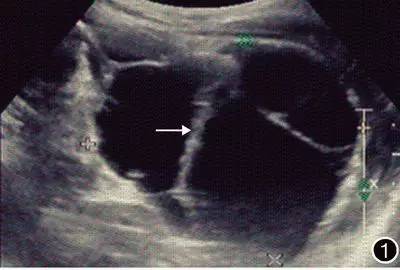

B超检查:左上腹(胰尾脾肾间隙)可见一巨大无回声区,大小约7.5cm×7.9cm×11.7cm,边界清晰,有壁回声,呈多房性分隔状,液性暗区回声均匀。见图1。彩色多普勒超声检查显示该回声区周围有少许血流信号,该回声区下方紧邻左肾,内侧紧邻腹主动脉。脾静脉及肾静脉在其内穿过。

图1 B超检查结果 左上腹可见一巨大的无回声区,边界清晰,有壁回声,呈多房性分隔状(→)

血管淋巴管瘤超声检查结果表现为边界锐利的囊性占位性病变。本例患者B超检查发现囊性占位性病变内部为无回声区,边界清晰,内部呈多房性分隔。超声检查对此类肿瘤的诊断有参考价值,CT检查可进一步定性定位辅助诊断。CT表现为囊实性占位性病变,以囊性为多见,壁薄,囊腔大小不一,可表现为囊性低密度灶或等密度灶。增强时囊内部分无强化,实质部分及分隔动脉期轻度强化,静脉期及延迟期强化逐渐明显。血管淋巴管瘤内可见大量扩大的淋巴管和毛细血管,管腔内有淋巴液、少量淋巴细胞和红细胞,管壁间有淋巴细胞浸润。